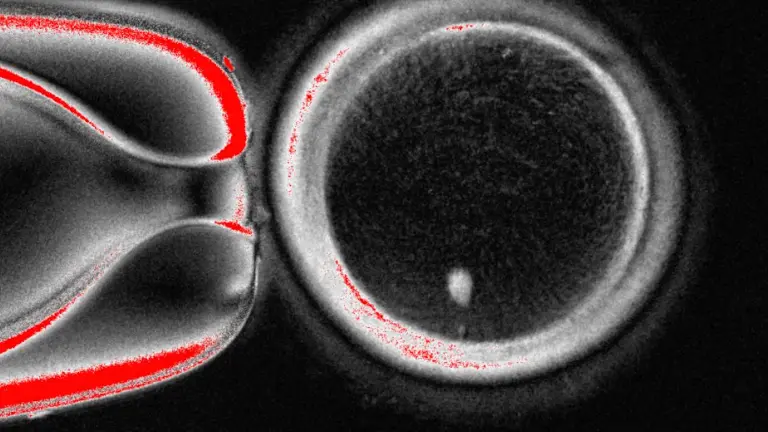

El equipo de OHSU extrajo el núcleo de una célula de óvulo humano y lo reemplazó con el núcleo de una célula de piel humana. Pero una célula de piel contiene dos conjuntos de cromosomas, y se supone que los óvulos y los espermatozoides deben contener solo un conjunto que se combine durante la fertilización. Por lo tanto, los investigadores indujeron a las células similares a óvulos a descartar cromosomas adicionales, inyectaron espermatozoides donados y activaron el desarrollo post-fertilización.

Aproximadamente el 9% duró seis días en platos de laboratorio, alcanzando la etapa de blastocisto del desarrollo temprano del embrión, antes de que se detuviera el experimento.